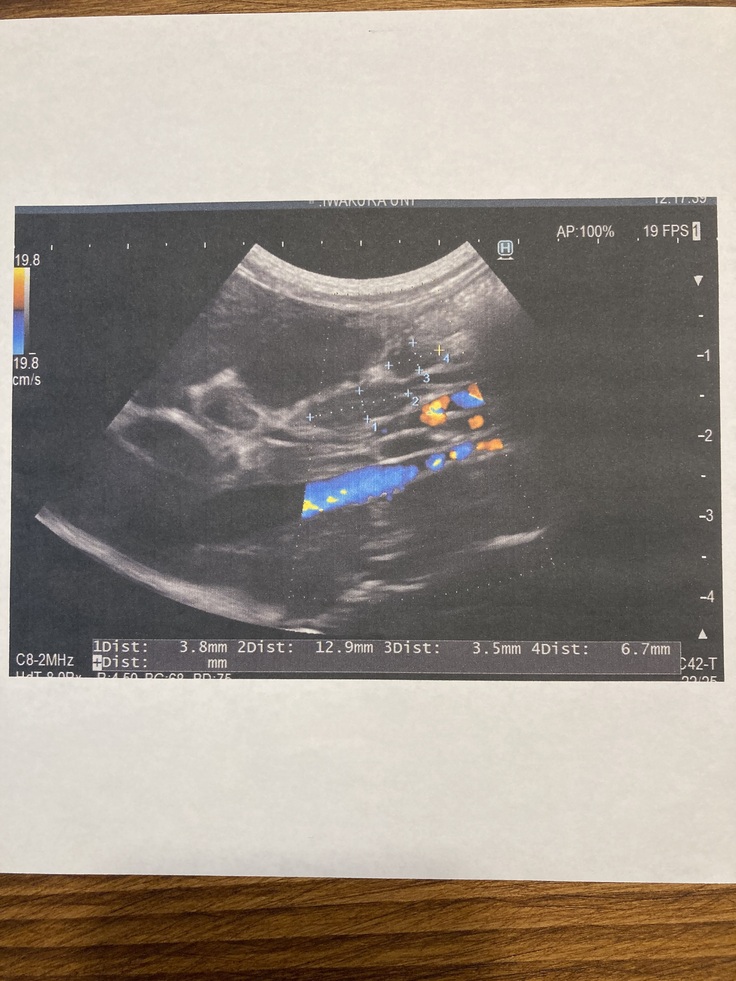

◎2021年7月24日(かかりつけの病院で)

外部での検査結果でもFIPであることが濃厚で、エコー検査の結果でもリンパ節に腫れが見られるとのことでした。医師からこの病気は、完全に治ることはなく、余生をいかに過ごさせるかを考えなければならない。余命は早くて1~2週間、長ければ数か月であると伝えられました。